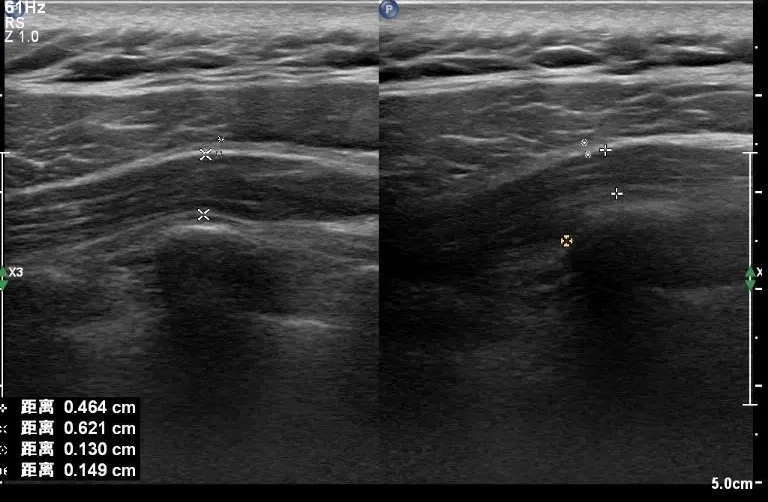

圖一:膝關(guān)節(jié)半月板損傷

圖二:腕管綜合癥